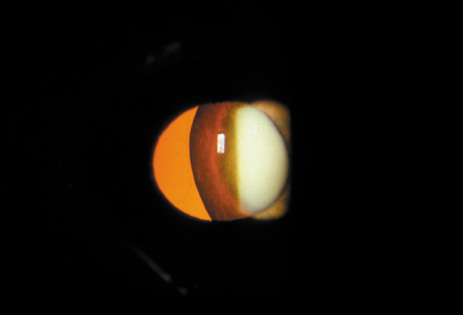

Cortical opacities have been clinically observed to develop earliest in the inferior half of the lens, especially the lower nasal quadrant.28 Epidemiologic29 and laboratory studies30 have suggested that cortical cataracts may be caused by ultraviolet rays from sunlight. The supraorbital margins may block the ultraviolet rays from falling over the upper part of the lens, thus making cortical cataract less frequent in the upper quadrants. Eventually these opacities also develop in the periphery in other quadrants, resulting in a circular array of spokes and peripheral cuneiform opacities (Fig. 9). Bands of central cortical fibers may become prominent and opacify centrally (Fig. 10). However, most cortical cataracts remain in the periphery for many years, even decades, before the central axis of the lens becomes involved, causing loss of vision late in the development of the cataract.

Fig. 9. Moderate cortical changes. Wedge-shaped (cuneiform) or spoke-like (wheel) peripheral changes are seen. These changes may be extensive but may not affect Snellen visual acuity since they occur in the periphery.

Fig. 10. Central cortical opacities. This type of cortical opacity may causes early diplopia and glare disability.